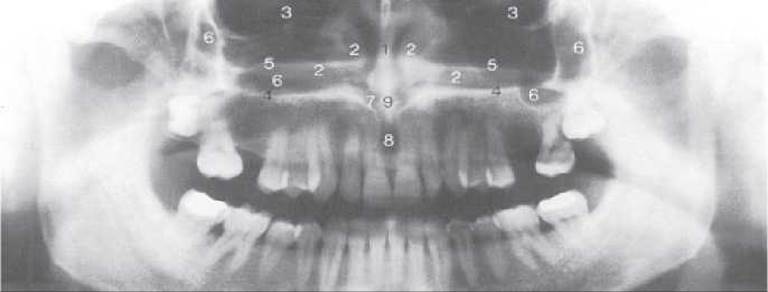

Ортопантомографія (панорамна томографія, пантомографія) - метод томографічного рентгенівського дослідження за якого на одній плівці одержують зображення томографічного шару верхньої та нижньої щелеп. Таке дослідження виконують на спеціальному рентгенівському апараті - ортопантомографі (мал. 299). Принцип роботи ортопантомографа: плівка в спеціальній касеті і рентгенівська трубка синхронно обертаються в протилежних напрямках навколо голови пацієнта (мал. 300). Пучок рентгенівського проміння проходить через вертикальну щілину діафрагми і поступово, у мірі його обертання, експонує всю плівку. Отримані зображення називаються ортопантомограмами, на яких знаходиться випрямлене розгорнуте зображення щелеп із зубами (мал. 301).

Переваги цього методу - швидкість одержання знімка, що несе інформацію про стан зубощелепної системи пацієнта в цілому, при відносно невисокому ступені опромінення. Проте є і недоліки - зображення щелеп і зубів на знімках викривляються та деформуються.

Мал. 301. Ортопантомограма.

Мал. 302. Анатомічні структури на ортопантомограмі: 1 - носова перегородка; 2 - Нижня носова раковина; 3 - Очна ямка; 4 - нижня стінка носової порожнини; 5 - горизонтальна пластинка піднебінної кістки; 6 - верхньощелепна пазуха; 7 - носовий вхід у різцевий канал; 8 - різцевий отвір; 9 - передня носова ость та носовий гребінь верхньої щелепи.